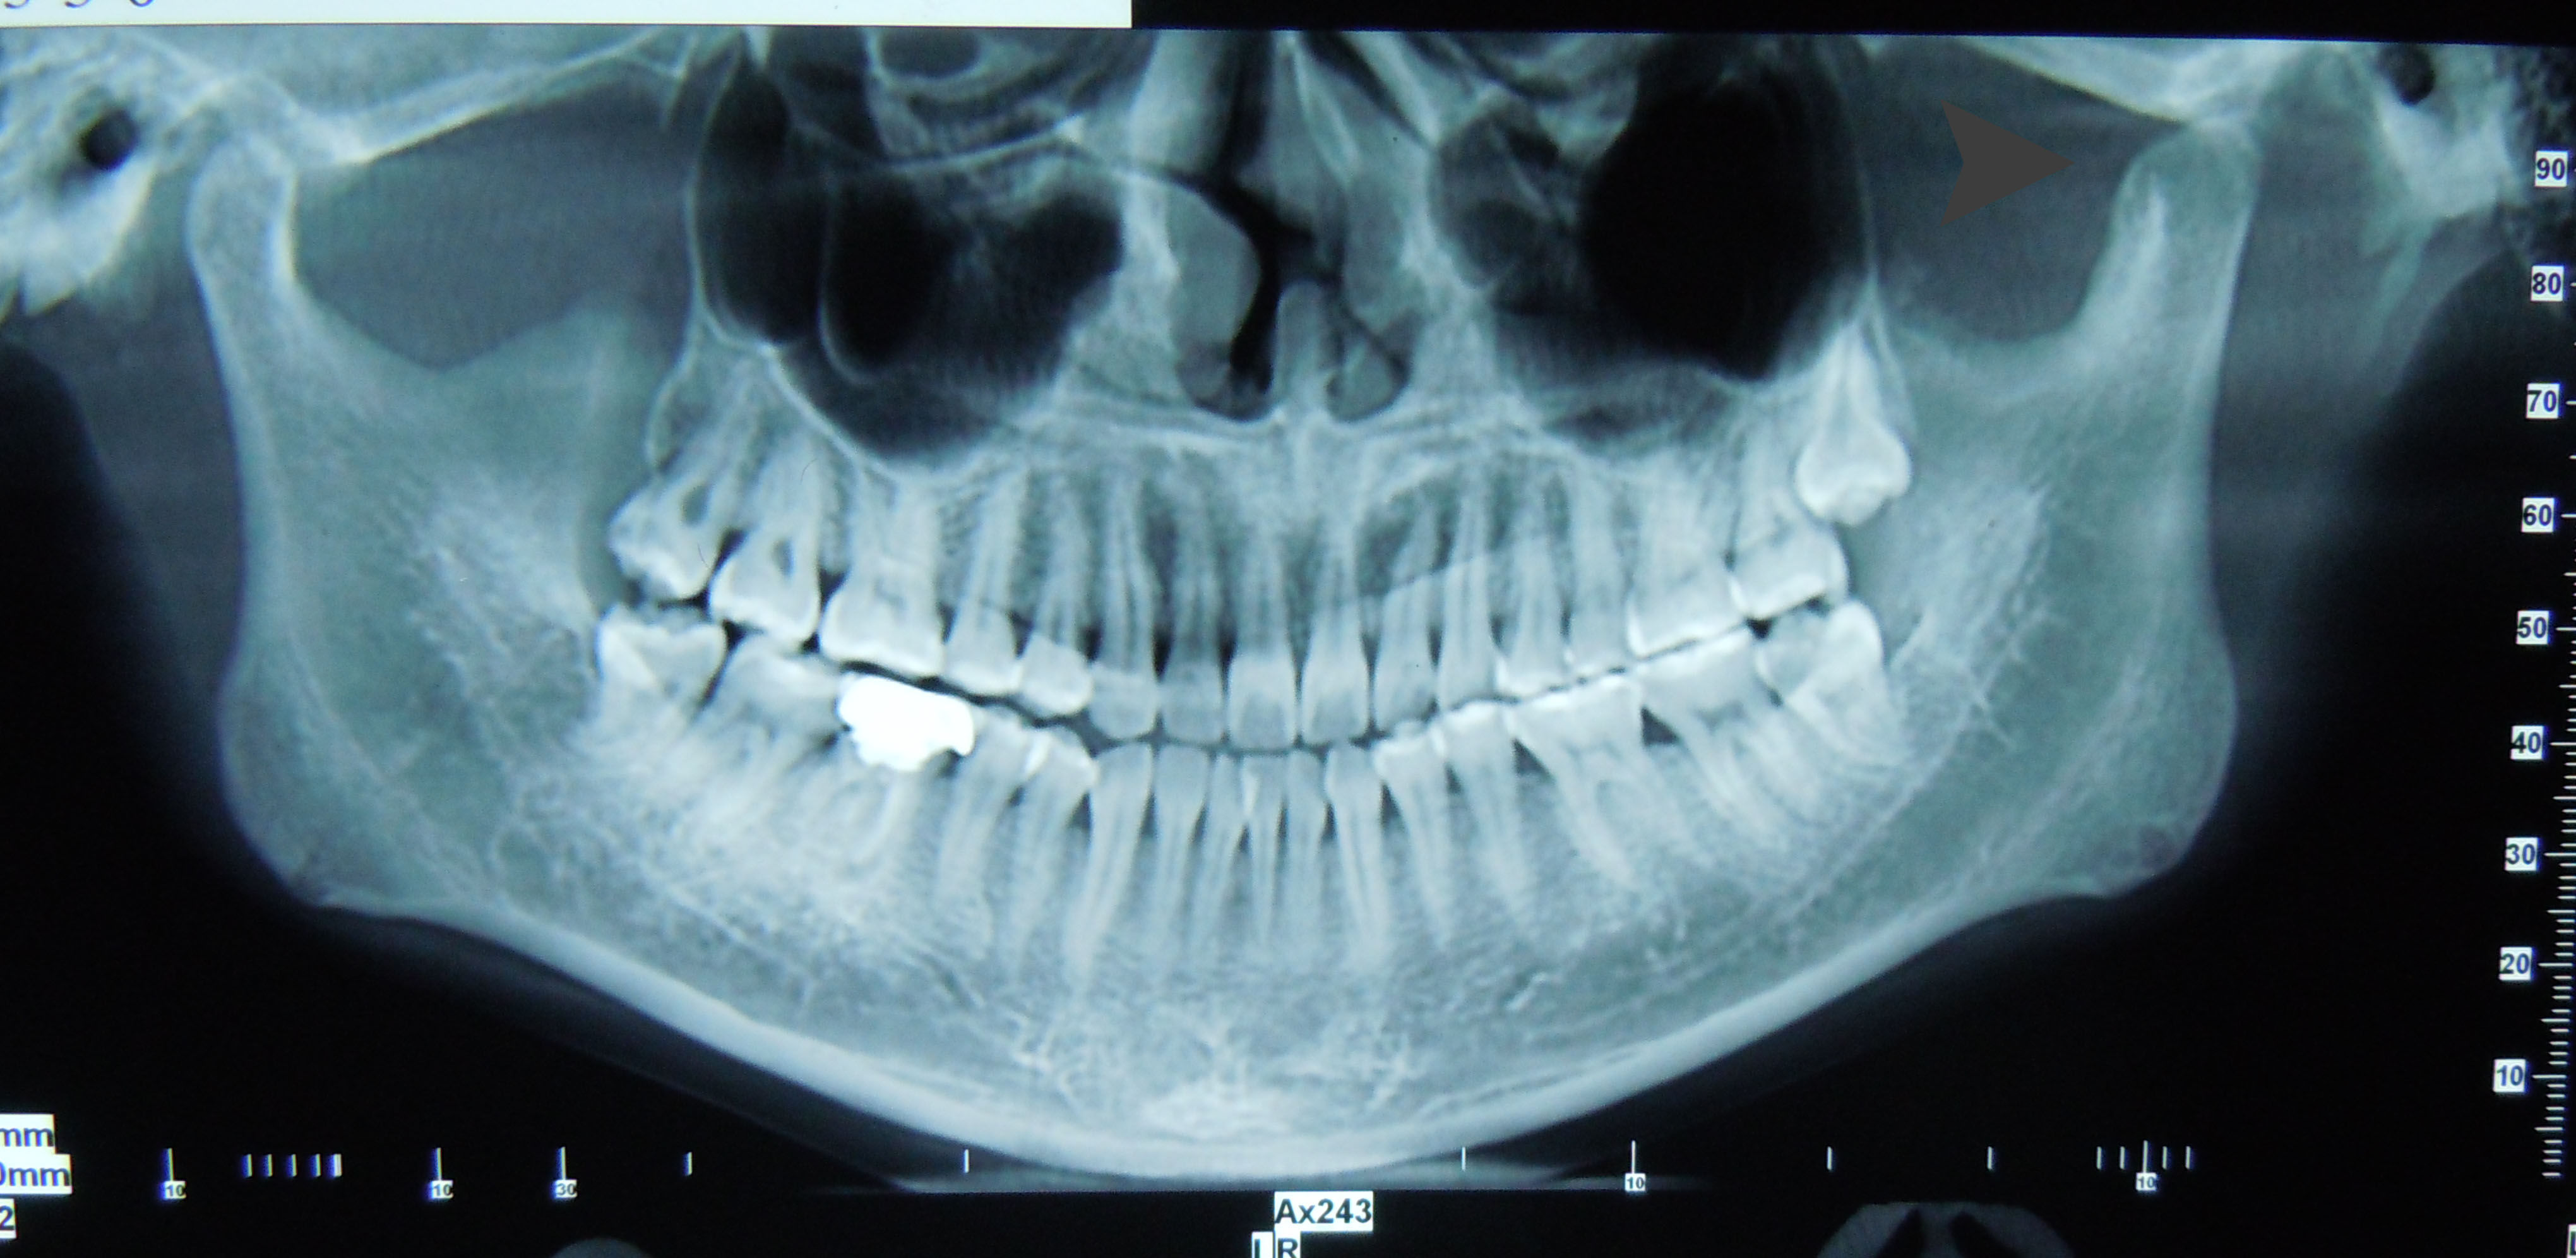

颞下颌关节脱位是指髁突滑出关节窝以外超越了关节运动的正常限度以致不能自行复回原位。多数是颞下颌关节髁突前方脱位。最主要的临床表现是闭不上嘴。辅助检查:X线片可见髁突脱位于关节结节前上方。

来我院就诊时左侧关节窝空虚,前牙反颌,偏斜

要求拍CT,ct显示左侧髁突骨质改建良好,可以考虑正畸治疗这种反颌,后来我们考虑这个人都27岁了,对面容要求也不高了,而且牵引钉拉髁突向后的力量不足,是因为上下颌牙尖的锁结很厉害,所以建议戴薄稳定合垫,打开咬合,同时戴颏兜加大向后的力量,再观察一个月。